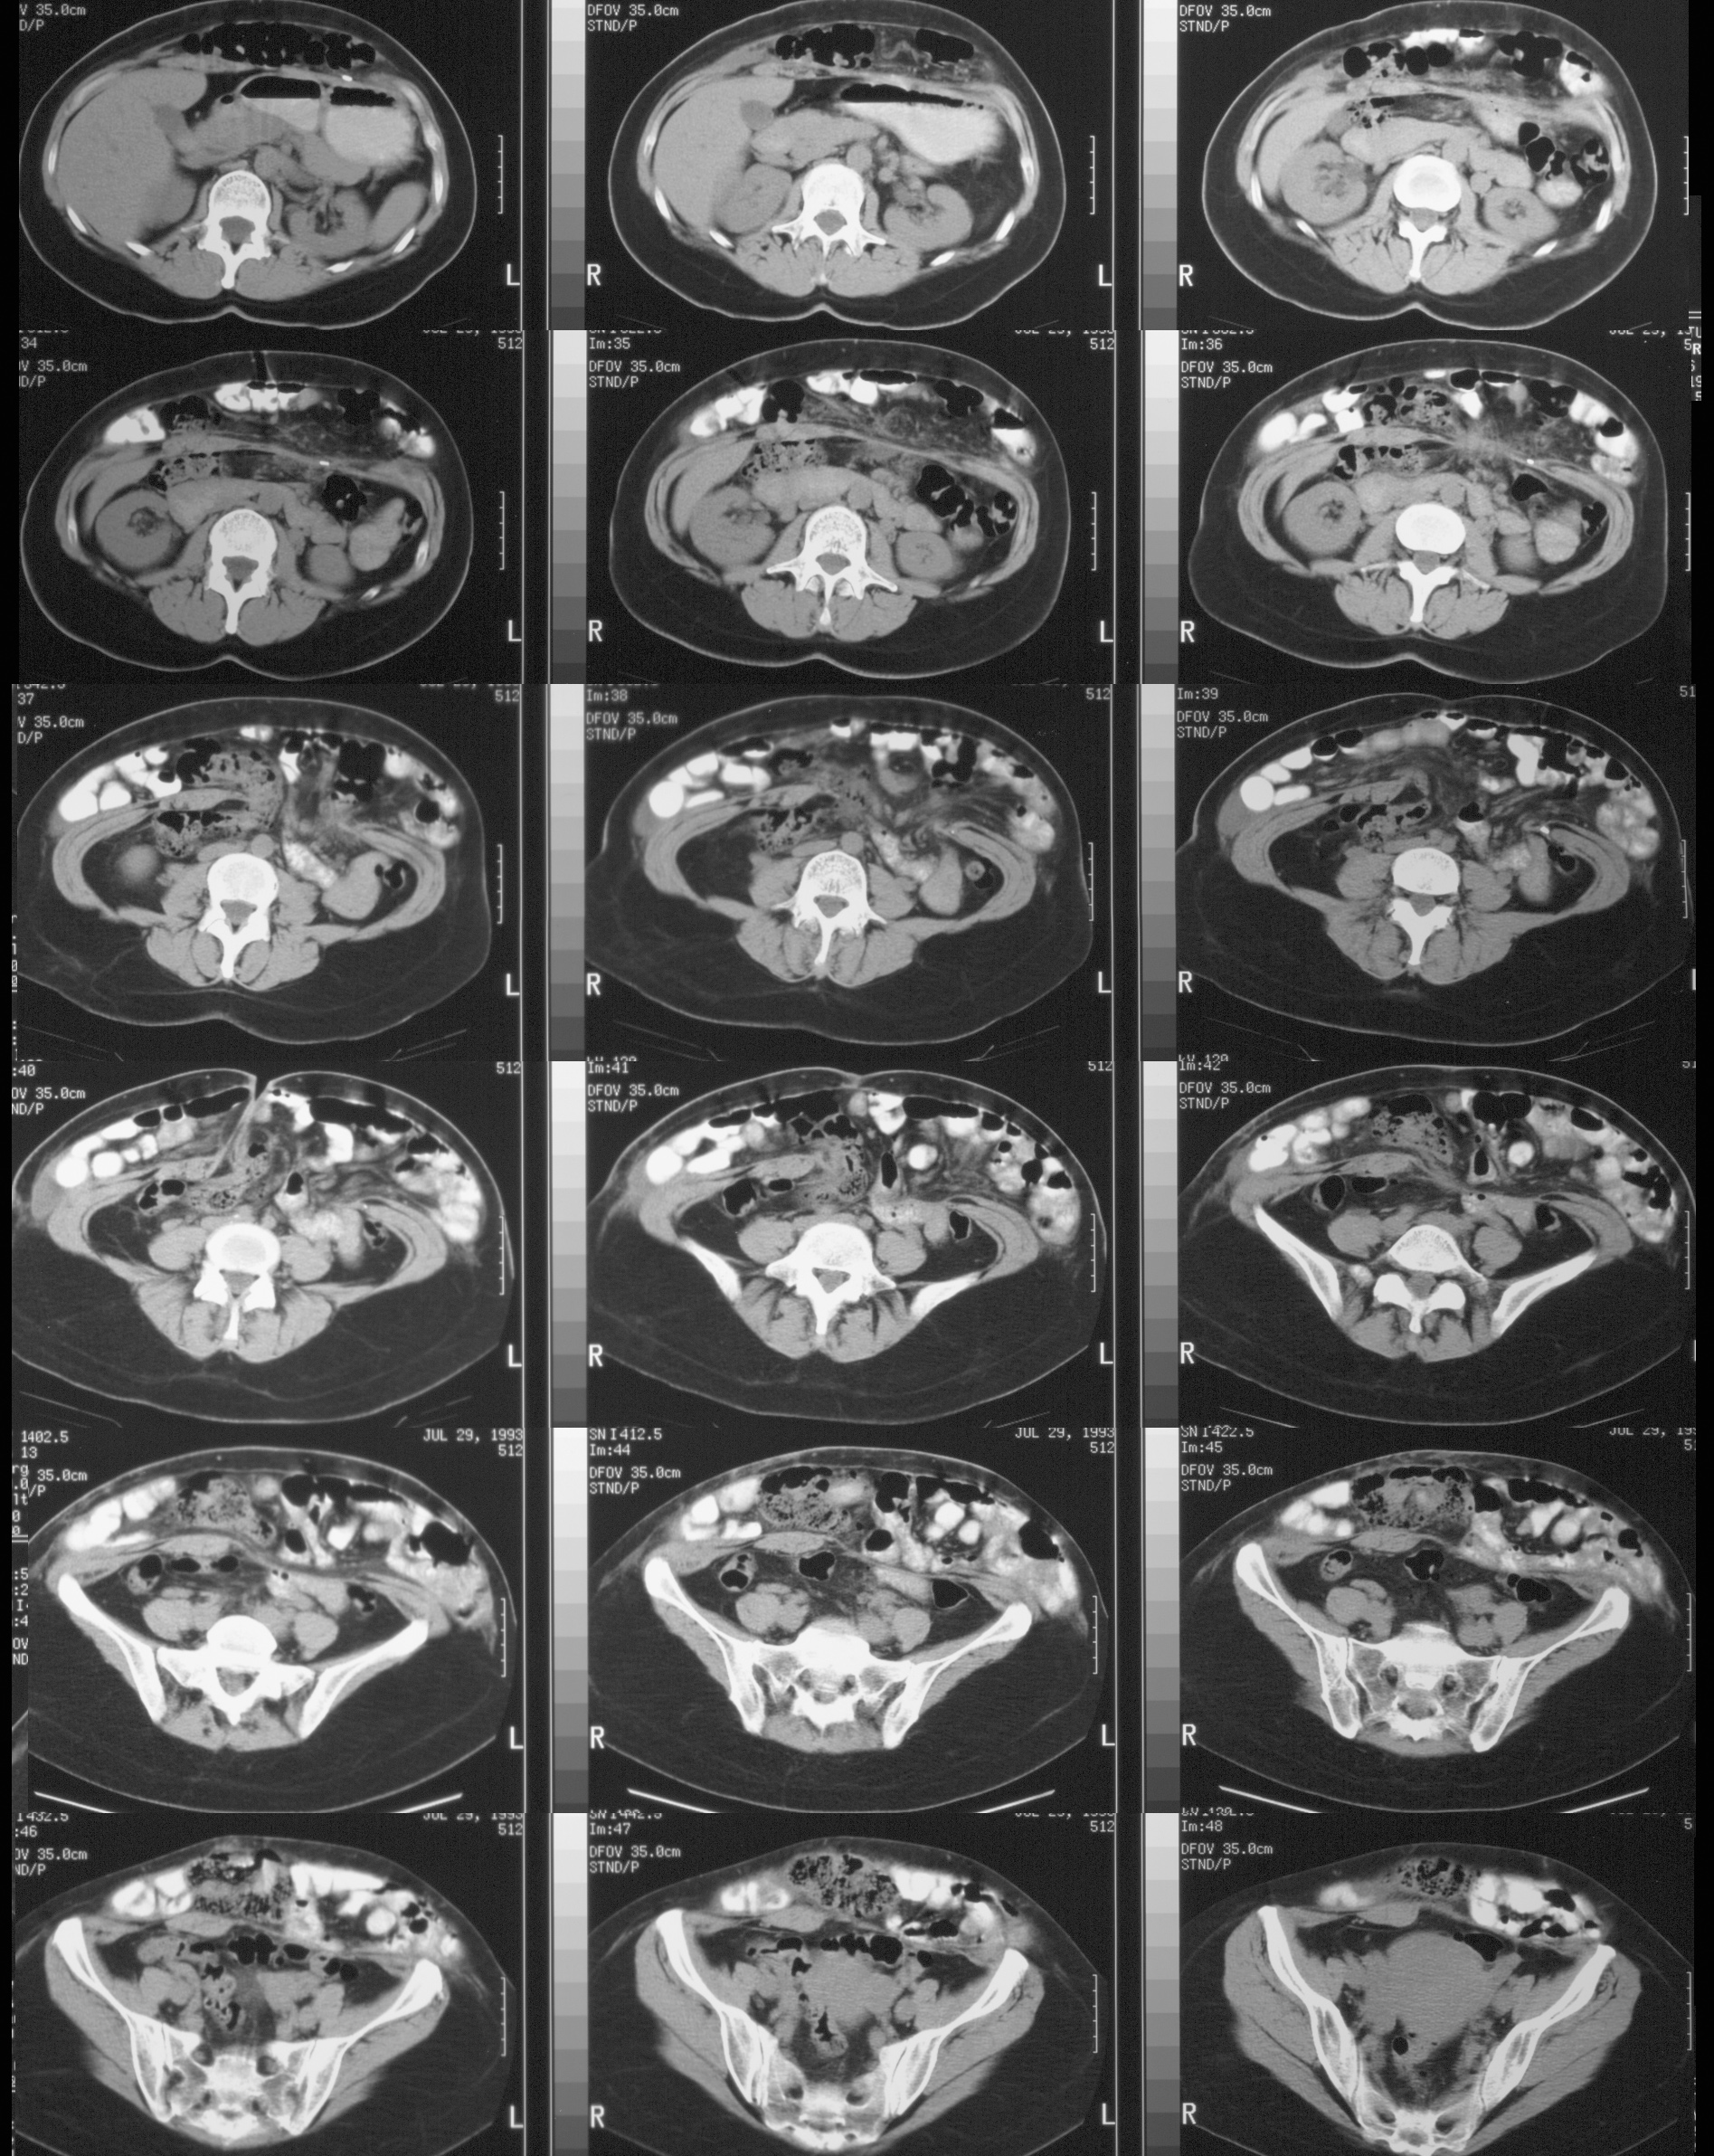

◂Breast Anatomy